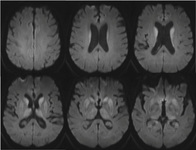

RNM cranioencefálica: o sinal pulvinar (um termo que se refere à hiperintensidade pulvinar bilateral) em um paciente com doença de Creutzfeldt-Jakob em imagens ponderadas por difusão

Do acervo pessoal de Leo H. Wang; usado com permissão